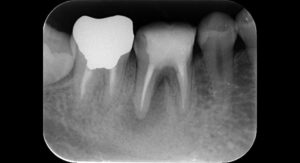

20代男性性の患者様です。

奥歯の根の先に透過像 (黒い影) を認めます。

精密根管治療を要する根尖性歯周炎の所見です。